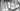

Ещё один случай одномоментной имплантации в жевательном отделе. Пациента отправили ко мне из другой клиники с просьбой провести операцию по удалению зуба ранее восстановленного культевой вкладкой и металлокерамической коронкой; на дистальном корне по данным КЛКТ имеет большой очаг деструкций кости.

Я был бы не я — если бы просто согласился и молча удалил зуб. Я всегда стараюсь минимизировать количество оперативных вмешательств, съеденных таблеток и уменьшить период реабилитации пациента.

Что было сделано: провели атравматичное удаление зуба 46, удалён воспалительный элемент в области дистального корня, установлен имплант, костная пластика, пластика слизистой, установлен формирователь десны.

В итоге: через 3 месяца пациент будет жевать новым зубом. А если бы мы пошли по «классике» то истории бы растянулась до 6—7 месяцев.

Время операции 45 мин.

Сложность 4/10